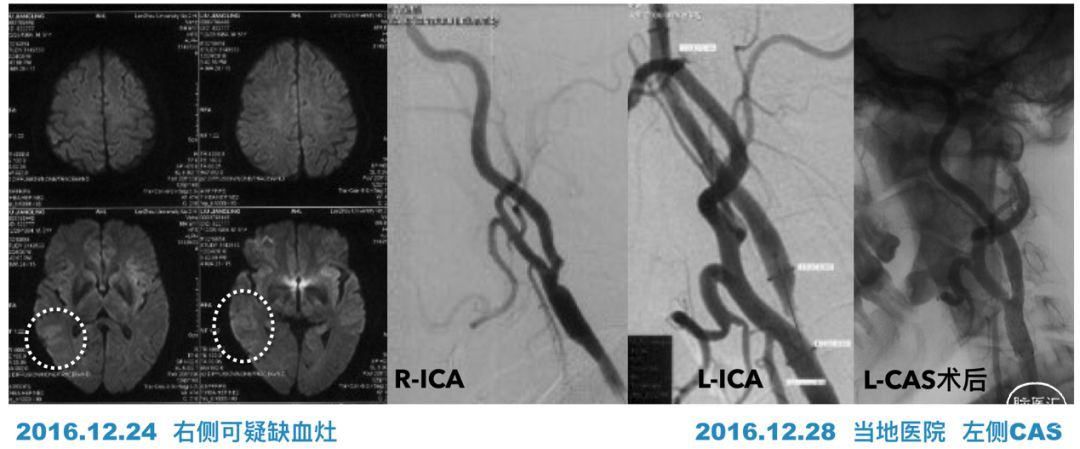

患者:男性,55岁,左侧肢体无力1月余收入院。患者3年前因左侧肢体无力曾在当地就诊,造影发现右侧ICA中度狭窄,但左侧ICA重度狭窄,所以做了左侧的颈动脉支架。

术后情况一直很好,直到1月前,患者反复多次出现左侧肢体力弱,MRI显示明确的右侧半球多发梗塞灶。判断机制应该是低灌注和栓塞都有的混合机制。

当地医院很快完成了造影检查,发现右侧ICA闭塞,通过前交通动脉和眼动脉代偿。

当地医院灌注检查提示:右侧半球灌注不足。

入院后我们首先对其进行超声检查,结果有点出乎我们的预料——极重度狭窄,而非闭塞![]() ,难道当地造影结果有误?

第三个病例,回顾3年前发病的时候,虽然右侧颈动脉当时还是中度狭窄,较左侧为轻,但疑似皮层梗塞提示我们有栓塞的可能性。那时的颈动脉可能就是一个容易复发的易损斑块,正如后来高分辨率核磁所显示的那样,大脂质核心伴斑块内出血。对于颈动脉狭窄而言,除了狭窄度,斑块的稳定性也是我们必须重视的。